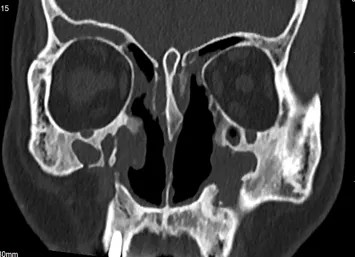

术后

经过两个小时惊心动魄的精细操作,手术结束,那颗3×4厘米的巨大骨瘤也被完整取出!

未发生脑脊液漏,没有大出血,视神经和筛前动脉等重要组织均保护完好。